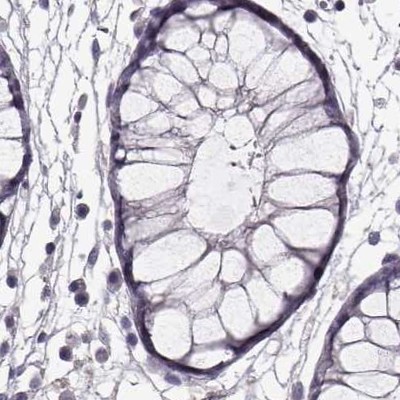

Immunohistochemical staining of human colon, eye, retina, liver and lymph node using Anti-GRK1 antibody HPA035200 (A) shows similar protein distribution across tissues to independent antibody HPA059376 (B).